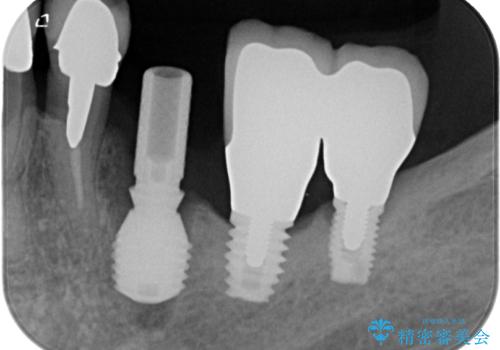

そのため、当院に新しく導入した手法により、抜歯をした日にインプラントを埋入し、そのままを仮歯を装着することで、他の歯への負担を軽減する計画を立てました。

インプラント埋入時に植立具合の安定性を測定したところ、十分な数値が得られたため、速やかに仮歯を装着して咬合回復をさせることができました。

抜歯を含めた外科処置を1回に抑えることができ、あっという間に治療を終えることができました。